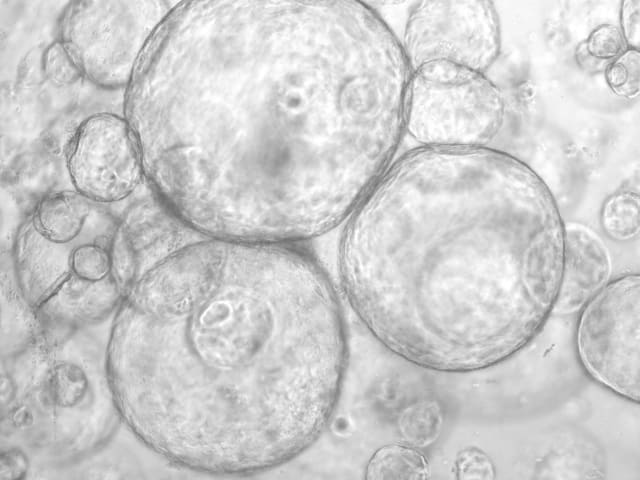

Zellen, die in einer Matrix eine beerenförmige Struktur ausbilden, typischerweise mit einem Hohlraum in der Mitte sowie inneren und äusseren Zellen. Organoide werden für das Projekt aus Gewebeproben von Patientinnen und Patienten gezüchtet. Auf diese Weise können zum Beispiel Wirkstoff-Wirkungen und die Entstehung von Tumoren untersucht werden. (Sven-Thorsten Liffers, Siveke Labor)